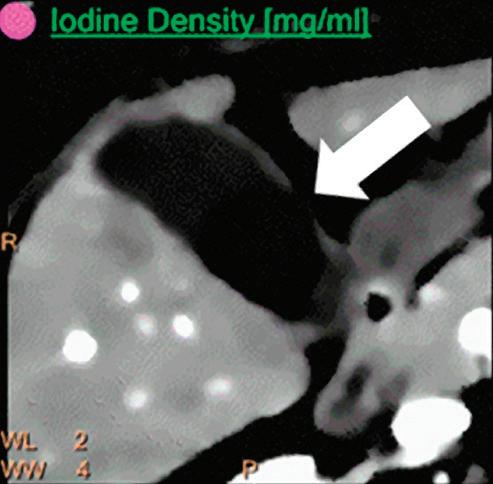

Iodine Density [mg/ml]

Also referred to as iodine map. This is a quantitative iodine image where voxel values are proportional and scaled to the iodine true concentration in units of mg/ml. Voxels without iodine content have zero iodine and hence are black (Figure 3).

Note: The algorithm includes a low bone removal threshold. Voxels with Ca content below the threshold are classified as containing iodine. The accuracy measured on a Gammex phantom with various concentrations of iodine (up to 20 mg/ml) show an iodine quantification to within 0.3 mg/ml, for both the Iodine no Water and iodine density measurements.21 In clinical conditions, an iodine concentration measurement of 0.5 mg/ml should be considered as the lower threshold for iodine uptake.

Patient presented to the emergency department with abdominal pain. The conventional CT does not reveal any abnormality in the gallbladder. In the middle row, spectral attenuation curves reveal two different materials: a first region of interest (purple) with a CT number that is increasing with energy, typical of a low Z effective element (below the Z effective value of water), and a second region of interest (blue) with a CT number that is decreasing with the energy, typical of a Z effective above water. The differentiation between the two materials cannot be performed based on the conventional CT because the two attenuation curves cross each other around 70 keV (where the attenuation is equivalent to the conventional CT). The lower row displays spectral results in the Magic Glass, from left to right: 40 keV image, 200 keV image, iodine density image, and Z effective map. A gallstone is clearly revealed on the 40 keV image and with an inverted contrast on the 200 keV image. The iodine density shows a perfusion defect of the gallbladder wall due to the compression with the gallstone (white arrow), and the Z effective helps us to determine the gallstone composition with a Z effective below 6.5 typical of a cholesterolic composition.